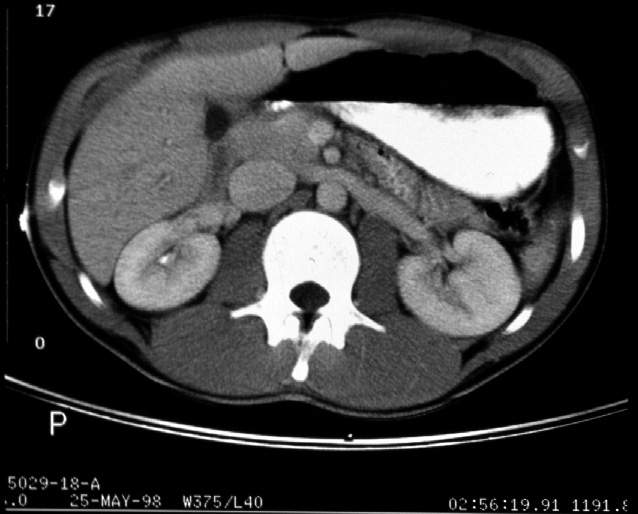

Identify -- stomach, liver, right kidney, left kidney, aorta, inferior

vena cava, pancreas, superior mesenteric artery and vein, spleen, small

intestine